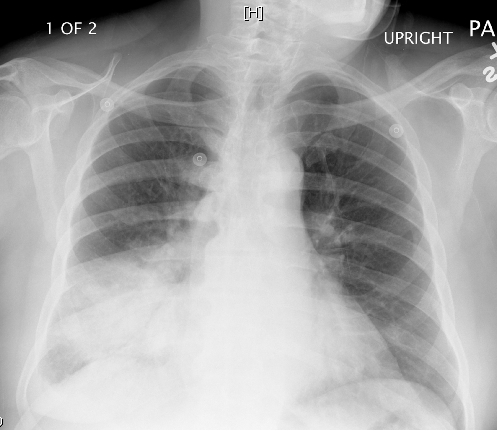

A 64-year-old man is evaluated for worsening cough and shortness of breath.  The patient has a history of hypertension and type 2 diabetes mellitus.  He smokes a pack of cigarettes daily and drinks alcohol occasionally.  Temperature is 38 C (100.4 F) , blood pressure is 140/82 mm Hg, and pulse is 92/min.  Lung auscultation reveals abnormal breath sounds.  Chest x-ray is shown below. A 64-year-old man is evaluated for worsening cough and shortness of breath.  The patient has a history of hypertension and type 2 diabetes mellitus.  He smokes a pack of cigarettes daily and drinks alcohol occasionally.  Temperature is 38 C (100.4 F) , blood pressure is 140/82 mm Hg, and pulse is 92/min.  Lung auscultation reveals abnormal breath sounds.  Chest x-ray is shown below.   Which of the following is the most likely cause of the observed pulmonary findings in this patient? A) Elevated pulmonary capillary hydrostatic pressure B) Exaggerated reactivity and inflammation of the airways C) Excessive fibroblast proliferation and extracellular matrix deposition D) Leakage of protein-rich fluid in the alveolar airspaces E) Mucous gland hyperplasia and inflammation in the large airways Which of the following is the most likely cause of the observed pulmonary findings in this patient?